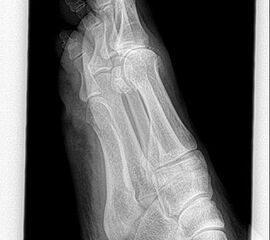

• Röntgenaufnahmen des Vorfußes (unter Belastung) im dorsoplantaren und seitlichen Strahlengang (Abb. 1a+b)

• Beurteilung des Erkankungsstadiums anhand der typischen Arthrosekriterien (Einteilung nach Regnauld) 2

• Beurteilung des Intermetatarsal-Winkels (IMA), des Hallux valgus-Winkels (HVA), mögliche Korrektur der des IMA von 6° durch alleinige Arthrodese, darüber hinaus evtl. zusätzliche MT-I-Korrektur notwendig 101112

• Beurteilung des Metatarsale-Index und der Zehenlänge DI und II, insbesondere nach Voroperationen hinsichtlich einer evtl. notwendigen Verlängerung des ersten Strahls durch Knochenspaninterposition